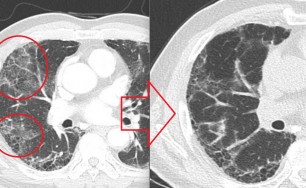

엑스레이,CT,혈액검사,천식검사 등 모든 검사에서 이상이 없다고 하며 이 병원에서는 비염 때문에 기침한다고, 저 병원에서는 역류성식도염 때문에 기침한다고, 또 어떤 병원에서는 틱(tic) 인거 같다고 , 심지어 어떤 병원에서는 평생 기침은 안고 가는거라고 이야기 하기도 합니다.

숨케어한의원에서는 전화예약을 받고 있습니다. 내원시 엑스레이, CT사진, 폐기능검사지를 가지고 오시면 자세한 상담이 가능합니다.